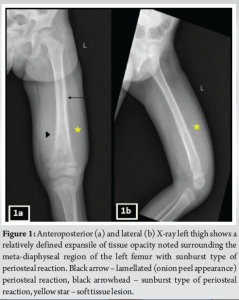

A 3-year-old female was brought to the pediatric orthopedic department with complaints of swelling over her left leg for 2 months. The swelling was insidious in onset, progressive in nature, associated with pain which was aggravated by movement, more at night, and associated with fever and local rise of temperature. According to the mother, weight loss and loss of appetite were noted. No history of abdominal pain. An X-ray of the left thigh was requested. It revealed an ill-defined subtle expansile lytic lesion in the diaphysis and distal metaphysis region of the left femur with the suggestion of lamellated (onion peel) and sunburst (in a few areas) types of periosteal reaction (Fig. 1). No evidence of fracture was noted. Laboratory results were as follows; white blood cell – 7220 cells/μL, hemoglobin – 6.8 g/dL (decreased), hematocrit – 24%, platelets – 190,000/μL, C-reactive protein (CRP) – 81.5 mg/L (raised) and lactate dehydrogenase (LDH) – 467.99 U/L (raised). The differential diagnosis of primary bone tumor (Ewing’s sarcoma > osteosarcoma) and osteomyelitis was considered initially. (High Resolution Sonography)left thigh was done, which revealed soft tissue showing significant vascularity on color Doppler with associated spiculated sunburst type of periosteal reaction (Fig. 2). A provisional diagnosis of primary bone tumor was made and as a part of metastatic screening, ultrasonography of the abdomen was advised. It revealed a large ill-defined heterogeneous retroperitoneal mass crossing the midline, encasing the aorta and its branches. The mass was seen insinuating beneath the aorta, lifting it off the vertebral column. Multiple enlarged pre/para-aortic lymph nodes and bilateral common, external, and internal iliac vessels were noted (Fig. 3). To further characterize the abdominal mass, the contrast-enhanced computed tomography (CECT) chest with the abdomen covering the thigh was done. It revealed a large heterogeneous solid mass lesion epicenter in the left suprarenal region measuring 10 × 6.6 × 11.6 cm in maximum orthogonal dimensions and crossing the midline. It shows multiple amorphous and chunky calcifications within. The mass is heterogeneously enhanced with areas of necrosis and is encasing and displacing the abdominal aorta. The left adrenal gland was not seen separately and mass is seen displacing the left kidney inferiorly and laterally. Multiple enlarged heterogeneously enhancing retroperitoneal lymph nodes are seen along with bony metastatic lesions (Fig. 4). Based on these findings, the primary diagnosis of left suprarenal neuroblastoma with multiple lymph-nodal and bony metastasis was made. Ultrasound (USG)-guided tru-cut biopsy of the left suprarenal mass was performed, which revealed small round blue cell tumor cells arranged in sheets and nests. Bone marrow trephine biopsy taken from bilateral posterior superior iliac spine revealed metastatic deposits of small round blue cell tumor. These cells were positive for synaptophysin, chromogranin, and cluster of differentiation-99 and negative for leukocyte common antigen confirming the diagnosis of neuroblastoma (Fig. 6). Eight cycles of neo-adjuvant chemotherapy were given to the patient. A metaiodobenzylguanidine scan post-chemotherapy revealed no residual bony metastasis. Positron emission tomography-computed tomography (PET-CT) was also done which revealed a non-fludeoxyglucose tissue mass noted in the left suprarenal region with an unremarkable musculoskeletal system. Follow-up CECT abdomen with the chest was done to assess chemotherapy response and for pre-operative planning which revealed a significant reduction in size and extent of the lesion with a significant reduction in number and size of retroperitoneal lymph nodes (Fig.5,7). Surgery was done and the residual lesion was removed. The patient is now on follow-up.